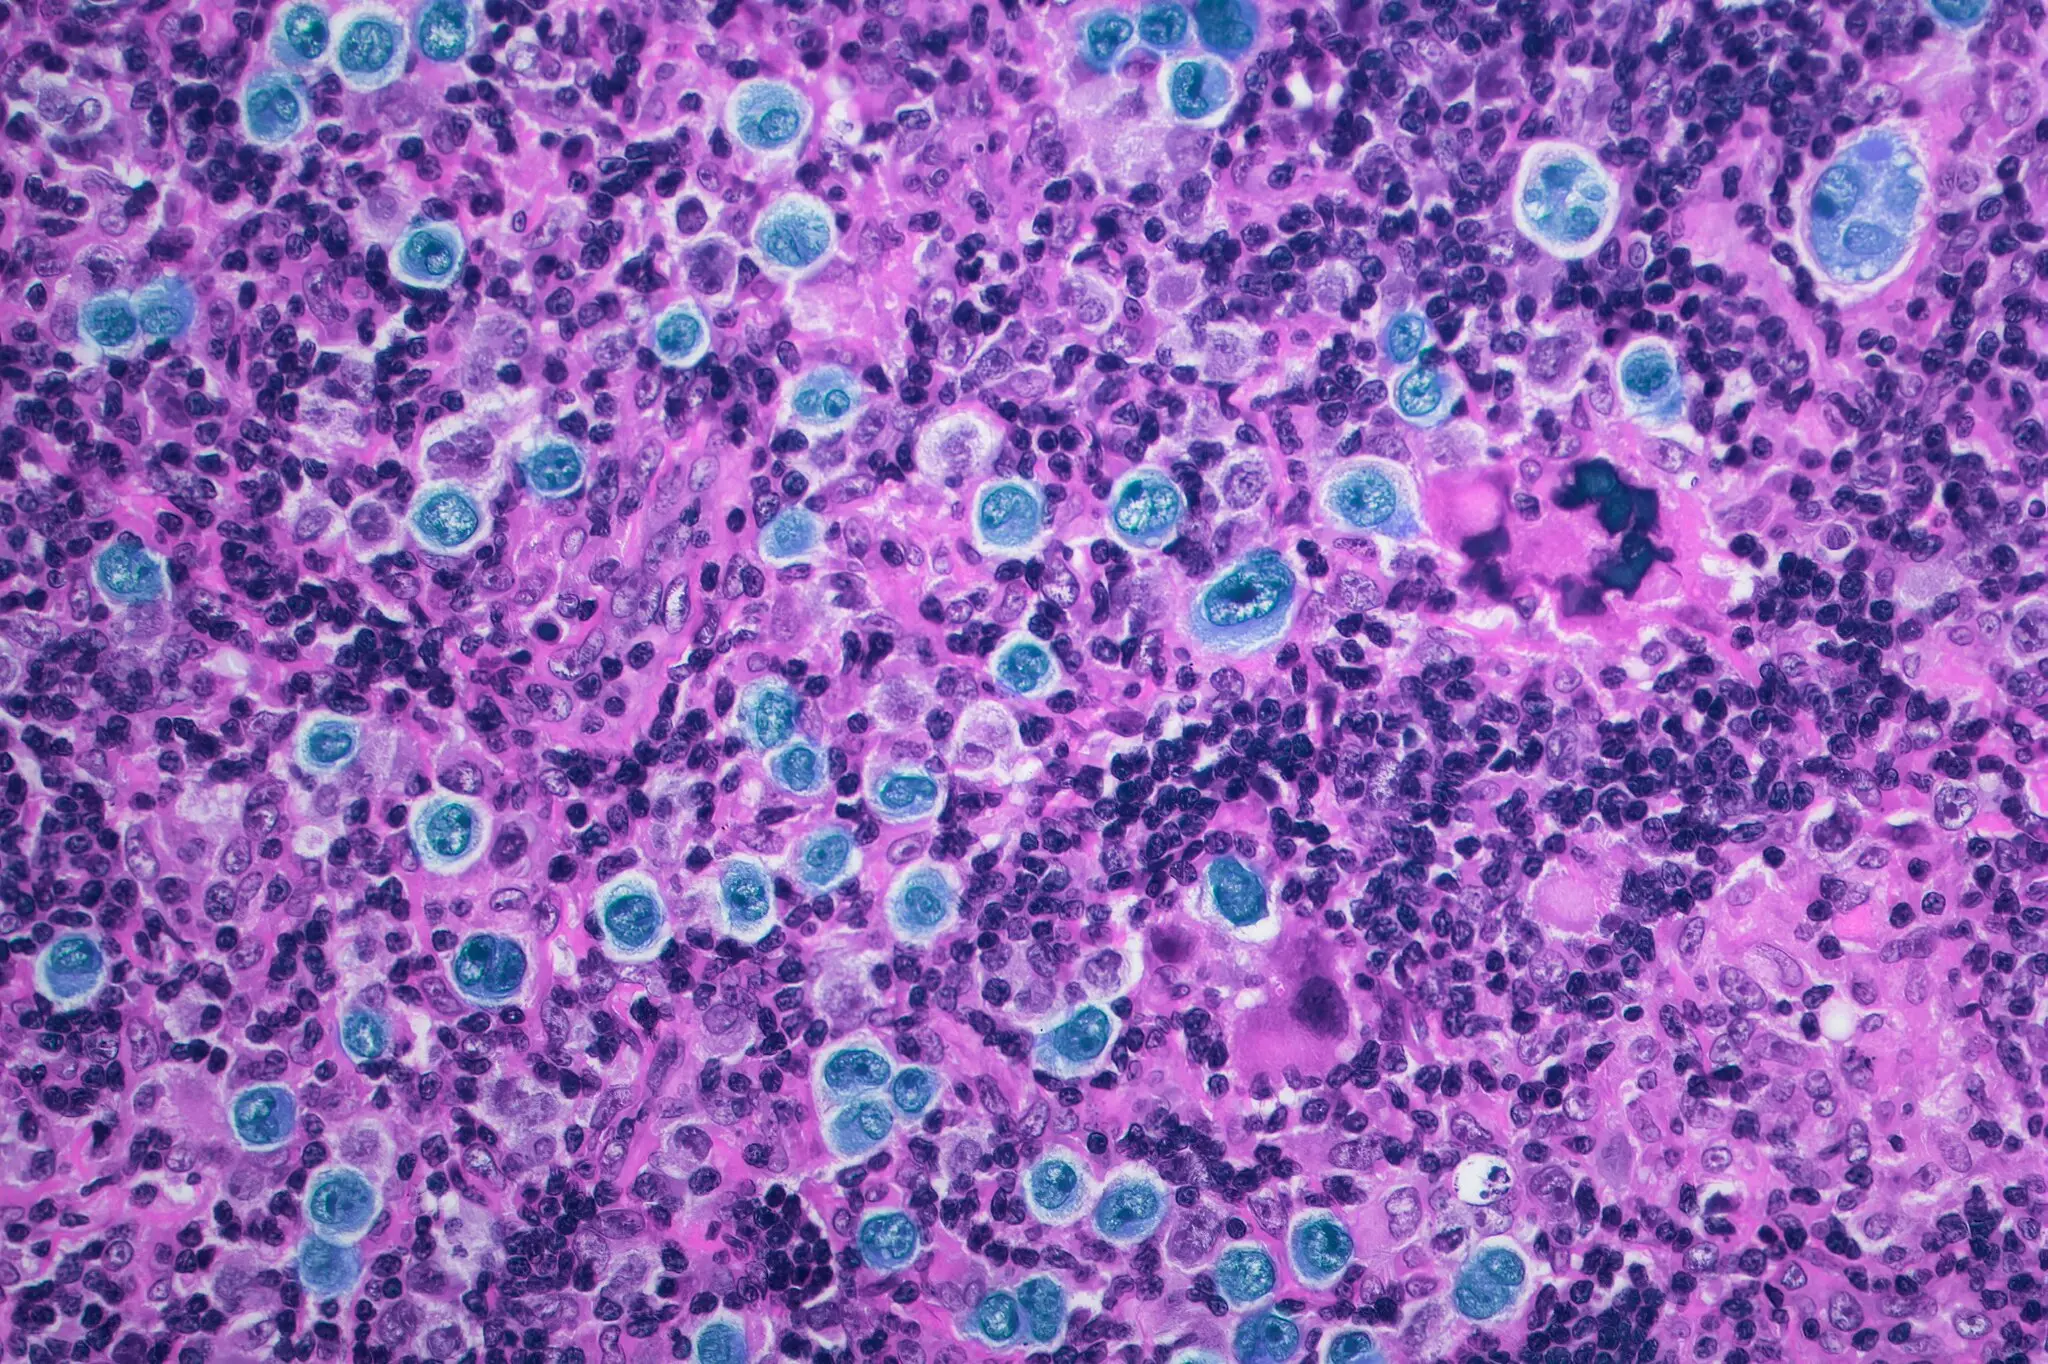

En experimentos de laboratorio con células de un cáncer en la sangre, el linfoma difuso de células B grandes, los investigadores diseñaron y construyeron moléculas que enganchaban dos proteínas: la BCL6, una proteína mutada de la que depende el cáncer para crecer y sobrevivir agresivamente, y una proteína normal de la célula que activa cualquier gen al que se acerca.

La nueva construcción, una molécula con forma de mancuerna, no se parece a nada que se haya visto en la naturaleza. La proteína BCL6, en un extremo de la mancuerna, guía a la molécula hacia los genes de muerte celular que forman parte del ADN de cada célula y se utilizan para deshacerse de las células que ya no son necesarias. Pero cuando una persona tiene un linfoma difuso de células B grandes, la proteína BCL6 desactiva esos genes de muerte celular, haciendo que las células se vuelvan casi inmortales.

Cuando la mancuerna, guiada por la proteína BCL6, se acerca a los genes que provocan la muerte celular, la proteína normal al extremo de la mancuerna arma a esos genes que provocan la muerte. A diferencia de otros procesos en la célula que pueden revertirse, la activación de los genes de la muerte celular es irreversible.